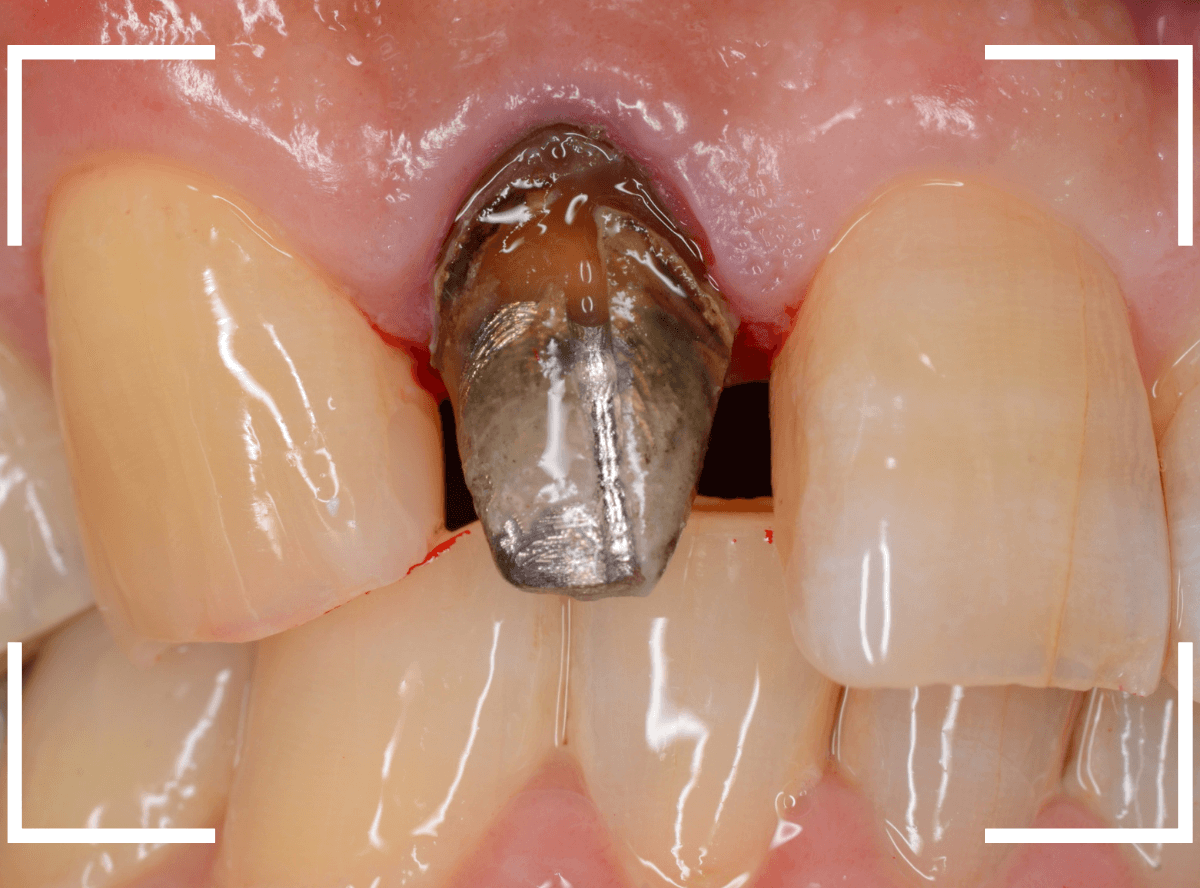

Case.16 保険のさし歯(レジン前装冠)をジルコニア・セラミックへ

以前に治療した上のさし歯を綺麗にやり直したいというご相談の患者さんです。

保険診療で行うさし歯「レジン前装冠」が入っています。

「レジン前装冠」は裏から撮影した写真を見ていただければわかるように、銀歯の上にレジン(プラスチック)を盛ったさし歯で、実質的には銀歯です。

銀歯の上にプラスチックを盛るために、歯をかなり大きく削る必要があったり、短期間で劣化・変色する(この方の差し歯も劣化してのっぺりした黄土色になっています)、金属の色素が歯肉に溶け出して歯肉が黒くなる(メタル・タトゥー)などのデメリットがあります。

治療をするためには、歯肉の形をトリミングするなどの若干の外科処置が必要です。

多少の痛みを伴いますが「頑張ります!」との事でしたので、そこも含めて治療する事になりました。

治療のためにさし歯を外すと、隣の歯のレジンの隙間に小さな虫歯が見つかりました。

これはさし歯を外した時あるあるなのですが、一緒に治療をします。

治療をすると、中まで入り込んだ虫歯でしたので、レジンを全て外して治療をし直します。

次に、隣の歯との高さに揃えるために、歯肉をメスで切開して、そこに合わせて歯の形を形成しなおします。

この形に合わせた仮歯を製作し、歯肉が落ち着くまでしばらく経過観察します。

痛みが引き、歯肉の形が整ってきたところで、型をとってさし歯を製作します。

今回は、ジルコニア・セラミックで製作する事になりました。

模型上で精密に制作します。

ジルコニア・セラミックは歯の内側や見えない部分にも一切金属を使用しないさし歯ですので、治療後の金属色で悩むこともありませんので、オススメです。